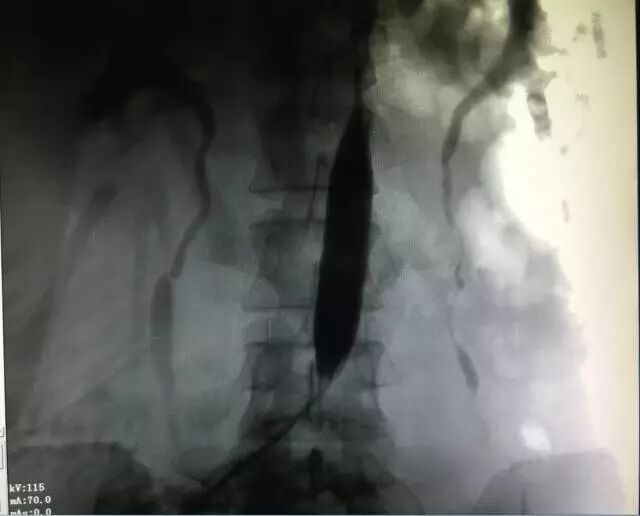

显示屏上清晰显示出孕妇腹主动脉中的球囊

但李女士已经有2次剖宫产史,子宫前壁局部极薄,加上胎盘植入情况极为严重,如果进行传统剖宫产,孕妇术中将出现巨大出血量,甚至危及生命

慎重考虑后,主治医师牛建民主任毅然决定采取“动脉球囊预置术+剖宫产术”的新技术,以减少术中出血,尽量保住子宫。经过3天的精心准备,手术最终成功实施。